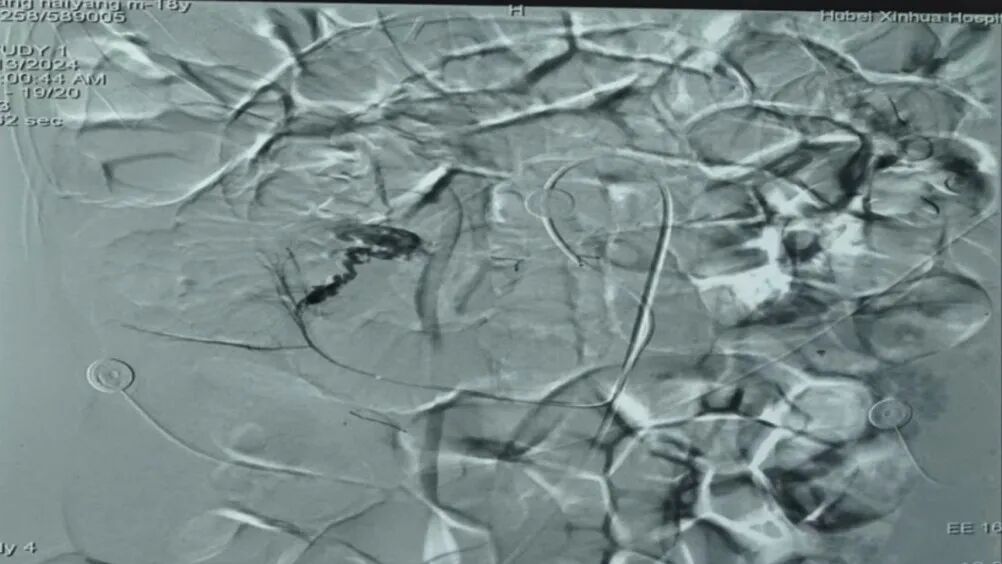

急诊腹腔动脉造影确定出血点

小肠出血的诊断及定位是临床比较棘手的问题,为了尽快明确出血部位和原因,抢救患者生命,医生迅速启动了MDT多学科诊疗,邀请放射介入科及普外科参与救治。